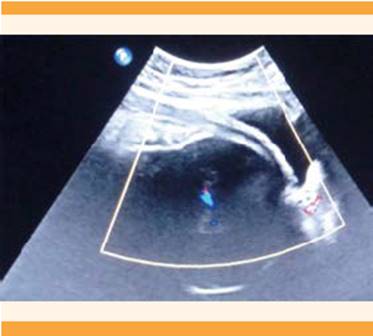

En la valoración obstétrica no se encontraron contraindicaciones para terminar el embarazo mediante parto; sin embargo, debido a la extensión y localización del hemangioma, las malformaciones vasculares y el alto riesgo de morbilidad, y posibilidades de hemorragia, trombosis e infección se valoró el riesgo-beneficio de la cesárea. Se llevaron a cabo estudios preoperatorios: biometría hemática, tiempos de coagulación y fibrinógeno que se reportaron en parámetros normales. En el ultrasonograma Doppler dirigido al segmento uterino no se observó incremento en la vasculatura (Figura 6,7y8). El principal diagnóstico diferencial consiste en descartar una fístula arteriovenosa en la extremidad hipertrófica, que integra el diagnóstico de síndrome Klippel-Trenaunay-Weber, se planteó la posibilidad de practicar estudios de extensión; sin embargo, por la necesidad de utilizar medios de contraste y al encontrarse en el tercer trimestre del embarazo se decidió posponer este estudio hasta la finalización del embarazo.

Thumbnail

Ultrasonograma Doppler dirigido al segmento uterino, sin incremento

de la vascularidad.

Figura 6

Ultrasonograma Doppler dirigido al segmento uterino, sin incremento de la vascularidad.

Ultrasonograma Doppler del segmento uterino, sin incremento en la

vasculatura.

Figura 7

Ultrasonograma Doppler del segmento uterino, sin incremento en la vasculatura.

Ultrasonograma Doppler del segmento uterino, con vascularidad

normal.

Figura 8

Ultrasonograma Doppler del segmento uterino, con vascularidad normal.